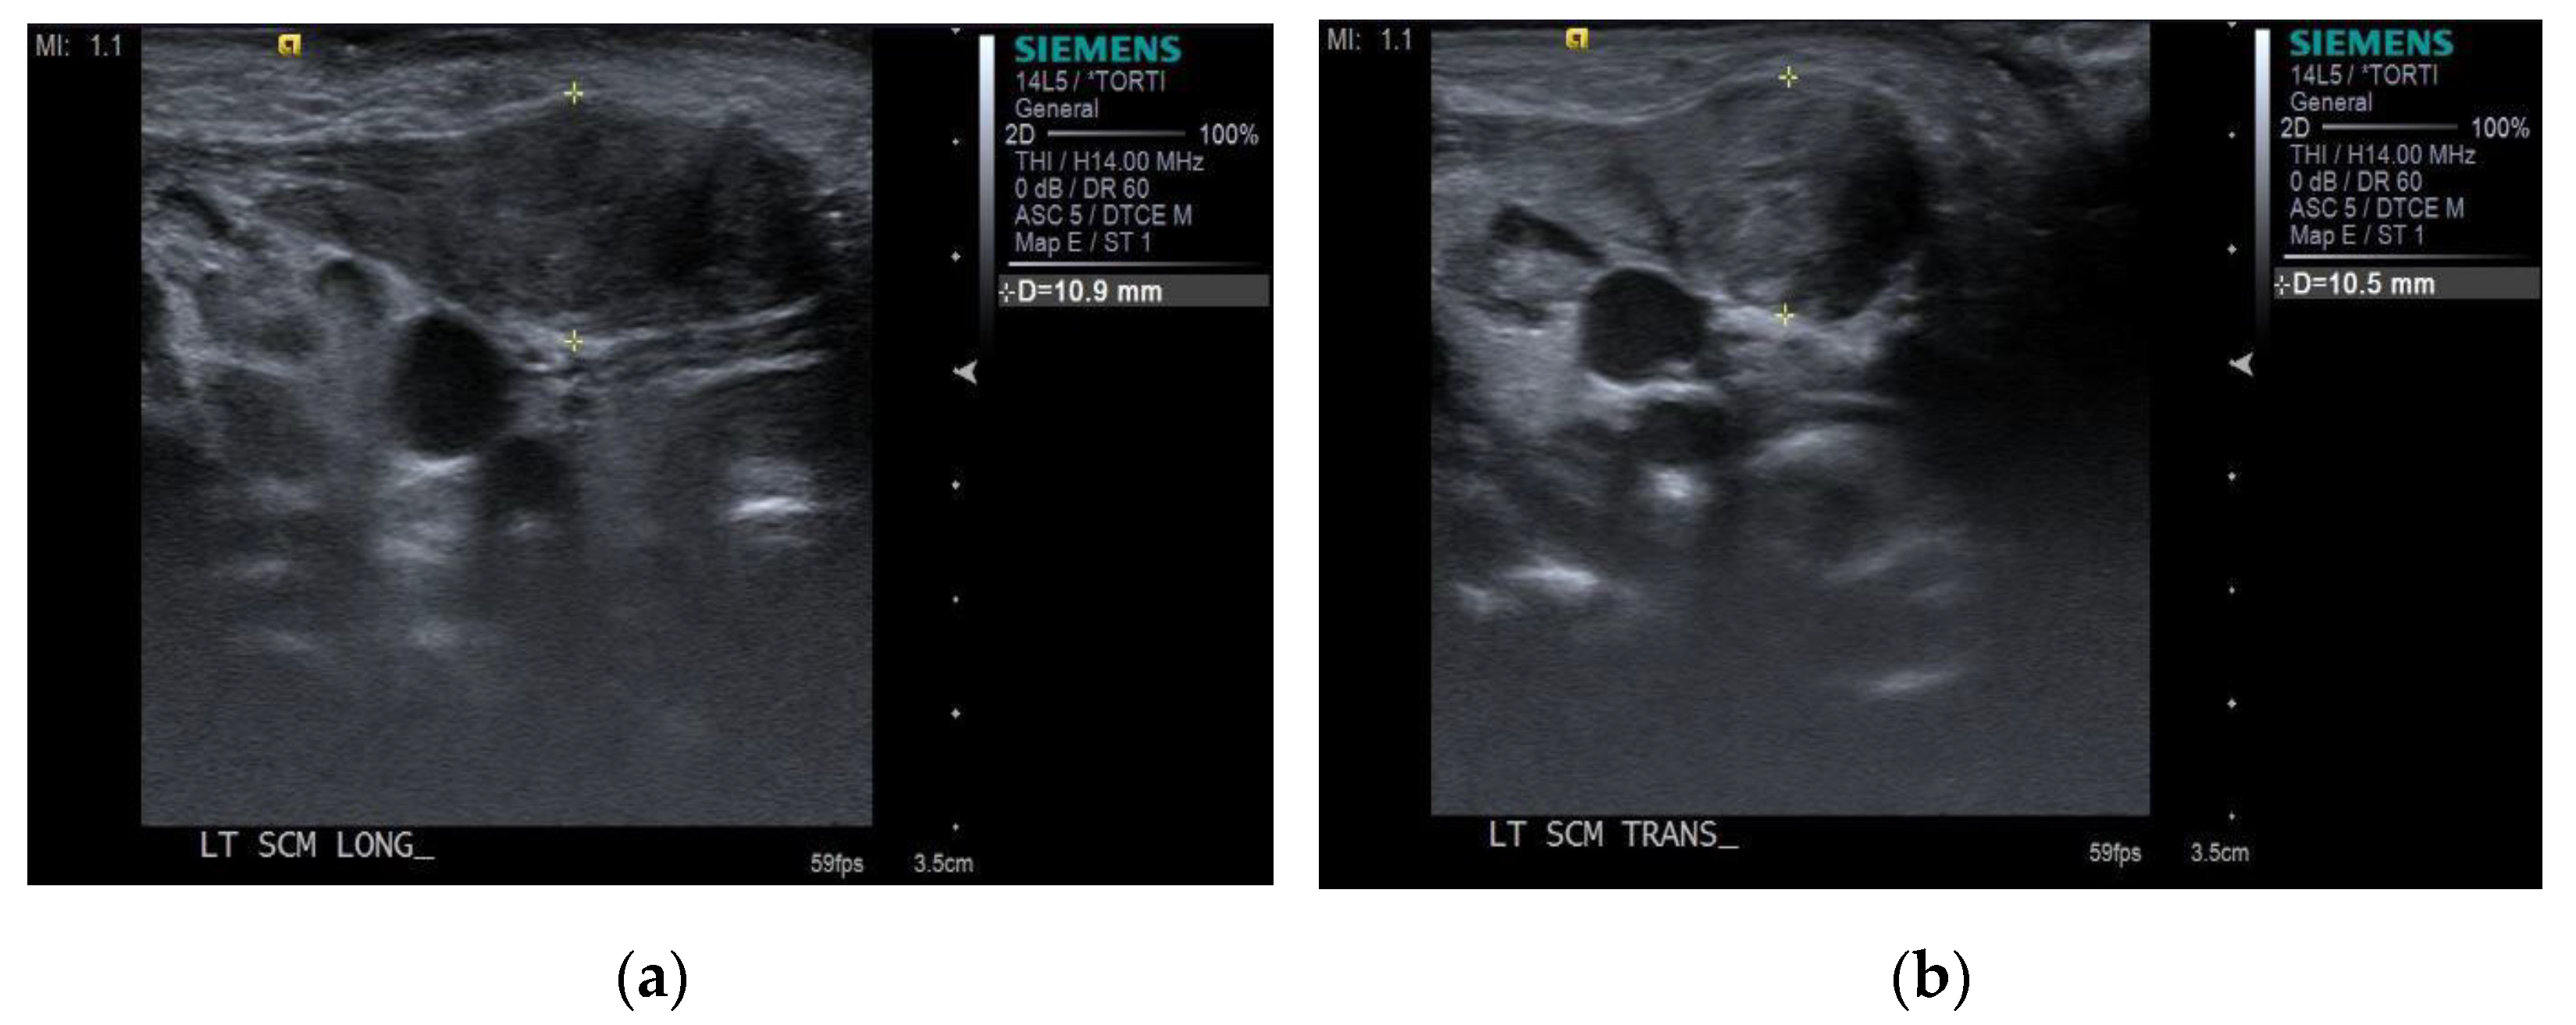

- Hwang, D.; Shin, Y.J.; Choi, J.Y.; Jung, S.J.; Yang, S.S. Changes in muscle stiffness in infants with congenital muscular torticollis. Diagnostics 2019, 9, 8290. [Google Scholar] [CrossRef] [PubMed] [Green Version]